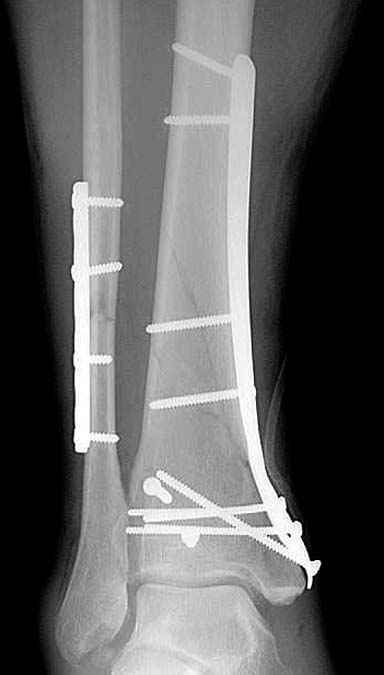

Приход анатомических преконтурированных тонких пластин с угловой стабильностью изменил методику лечения низких переломов. Современные пластины устанавливаются из минидоступов и разделяются на правые и левые. Можно установить латерально, медиально или спереди в полиаксиальных направлениях.

Без современных материалов создать хорошую фиксацию становится трудной задачей, и этот случай характерен тем, что достигнутую идеальную репозицию испортили старомодной техникой. Исследования показали, что спонгиозные шурупы в метафизарных частях не создают механические преимущества как считали раньше. Кортикальные винты менее агрессивны и не оставляют дефекта кости после их удаления.

Низкопрофильные преконтурированные пластины с угловой стабильностью создают меньше проблем с медиальным покрытием, а толстая пластина становится раздражителем после спадения отека.

Выбор метода фиксации зависит от того, что имеется под рукой, хотя, например, для Челнокова и для других коллег, без сомнения, был бы интрамедуллярный гвоздь. А другие коллеги предпочли бы аппаратное лечение, как говорят Курганские коллеги, дешево и без риска.

Здесь представлены несколько примеров снимков с осложнением, медиальная пластина, медиальная в комбинации с латеральной, метод Илизарова, а также сравнительные данные толщины медиальных пластин Synthes 4.4 mm, DePuy 3.2 mm.